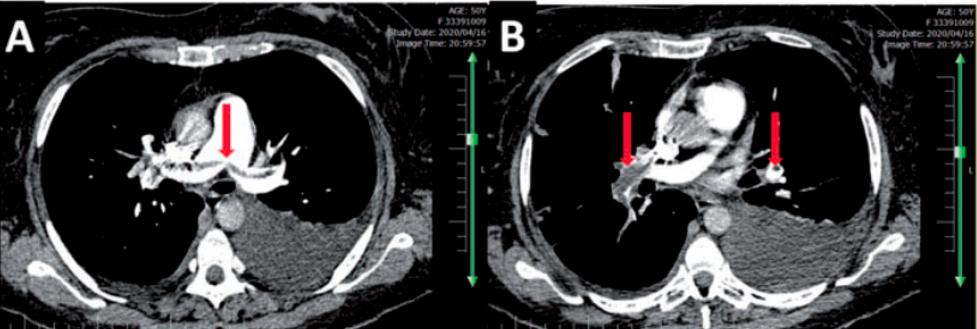

案例2: 大家再看看这个病例报告,是2020年Eur Heart J发表的文章,患者因为发烧、呼吸困难、干咳和疲劳就诊,核酸检测阳性,D-二聚体10ng/mL,是正常范围内;但入院第3天突发严重呼吸困难,SaO2降至74%,CTPA提示多发肺栓塞,两肺动脉的主干和远端有很多充盈缺损。

图:弥漫多发斑片影和胸膜下实变,伴有左侧胸膜渗出

图:主肺动脉可见骑跨型肺栓塞

患者接受肝素抗凝治疗7天后,病情稳定且核酸阴性出院。

这位患者带来的提示是什么?入院前D-二聚体正常,但入院后突然出现呼吸困难加重,这时也别忽视了血栓存在的可能,因为 D-二聚体是在不断动态变化的 ,有必要在入院第三天或第四天再进行D-二聚体的测试,也 一定要重视低氧血症的预测价值 。